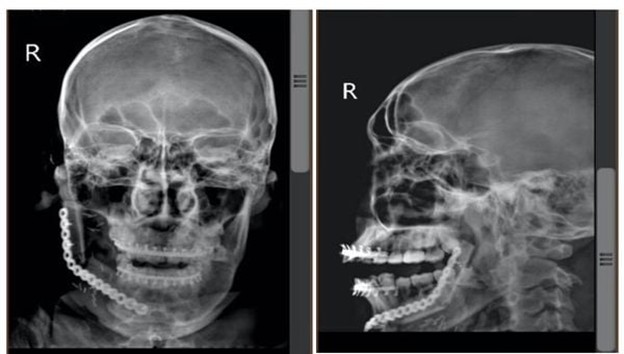

Anh D.P, 19 tuổi, ngụ tại Bình Phước, đến khám tại Bệnh viện Nhân dân 115 trong tình trạng có khối phồng gây biến dạng hoàn toàn vùng mặt phải, chức năng nhai bị giới hạn. Sau khi thăm khám và chụp CT- Scan, các bác sĩ nhận thấy khối u đã phá hủy xương từ răng số 46 đến lồi cầu xương hàm dưới phải.

Người bệnh được lên chương trình phẫu thuật cắt đoạn khối u xương hàm dưới với lề cắt an toàn 1cm, đồng thời xương hàm dưới được tái tạo bằng vạt xương mác tự do. Đây là một kỹ thuật phức tạp, yêu cầu kinh nghiệm, sự điêu luyện, tỉ mỉ và sức bền từ ekip phẫu thuật. Tuy nhiên, nhờ sự hỗ trợ bởi công nghệ 3D, giúp các bác sĩ mô phỏng trước từng thao tác cắt, ghép và tái tạo nên ca phẫu thuật diễn ra rất chính xác và nhanh chóng.

Sau 1 tuần phẫu thuật, người bệnh hồi phục tốt, dấu hiệu sinh tồn ổn định, vạt xương mác sống tốt, vết mổ khô, lành thương nhanh, chức năng ăn, nhai, vận động há ngậm và đặc biệt là thẩm mỹ gương mặt được cải thiện rõ rệt.